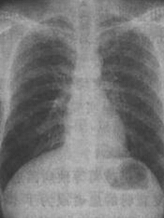

兩肺中下野見(jiàn)斑片狀陰影

4、x線檢查表現(xiàn)為兩肺紋理增粗,或兩肺中下野見(jiàn)斑片狀陰影;蛐∑瑺铌幱叭诤铣纱笃瑺铌幱,可合并大片肺不張。